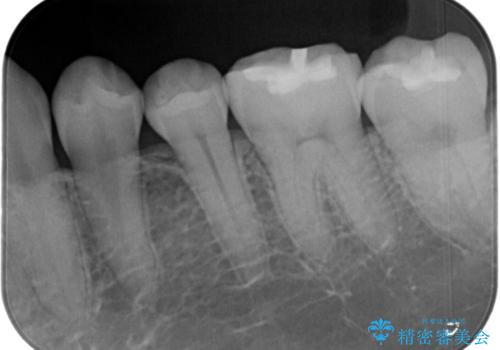

- 一番奥の歯の古い材料が劣化してしまい、欠けて黒くなっているのが気になるとの事でした。

詰め物のやりかえを提案したところ、セラミックインレーをご希望されたのでセラミックインレーにて治療をすることにしました。

古い材料と虫歯を除去して、型取りをしました。

適合も非常に良く、綺麗になりました。